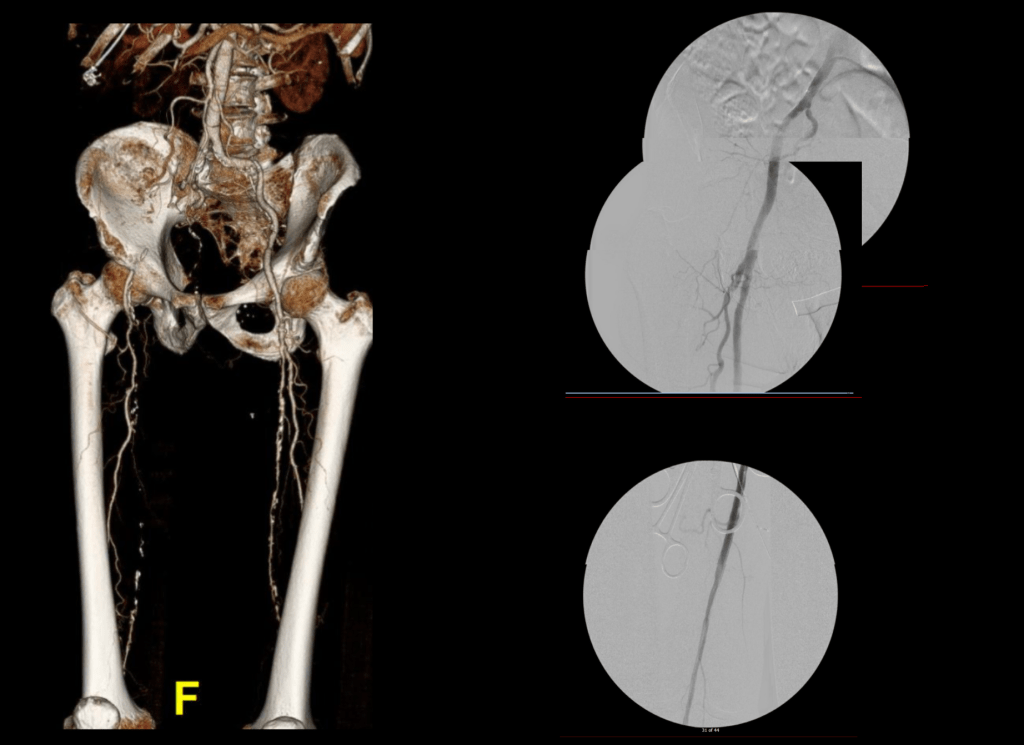

Let me show you one of the first cases I did after returning to Cleveland. I am now practicing at Fairview and Avon Hospitals, premier flagship hospitals in the Cleveland Clinic fleet, on Cleveland’s west side, and a patient arrived while I was on call with sudden onset of pain in his leg from a lack of blood flow. He had occlusive atherosclerotic plaque extending from his external iliac artery to the above knee popliteal artery causing ischemic rest pain.

I contacted LeMaitre Vascular and got in touch with your representative, L. Fisher, who promptly sent the Moll Ring Cutters I needed to perform a remote endarterectomy of the patient’s occlusive external iliac and superficial femoral artery plaque. The technical details of remote endarterectomy are have been covered in my blog (https://vascsurg.me/?s=endore), but in the end, through a 7cm incision in the groin (don’t believe the hype, this is minimally invasive), I restored his arteries to their original open condition. Shown below are the results. It was with great sadness that I heard that the LeMaitre Vascular equipment being sent were the last of the stock available in North America. The patient did very well, with the operation completed well before lunch, and is recovering rapidly from his small wound and big rescue. He gets to walk out of the hospital on two legs, but also with the surety that he avoided a major bypass operation, and avoided the short term gains of stenting from the aorta to the profunda -more peel packs and landfill items and a dubious long term durability. Hey, I even used a XenoSure patch on the common femoral.